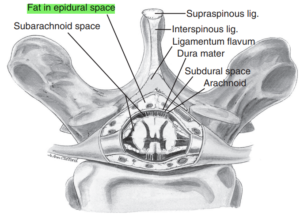

نخاع در تمام طول ستون فقرات، در داخل مهرهها و توسط سه لایه محافظ احاطه شده است.

خارجیترین لایه، دورا (Dura) نام دارد.

به فضای بین این لایه و سطح داخلی مهرههای ستون فقرات، فضای اپیدورال گفته میشود که با بافت چربی و عروق کوچک پر شده است.

در تصاویر زیر، این فضا با هایلایت سبز مشخص شده است.

به دلیل نزدیکی فضای اپیدورال به نخاع، میتوان برای بلاک اعصاب نخاعی (اعصابی که مستقیماً از نخاع خارج میشوند) داروهای بیحسی را به داخل این فضا تزریق کرد.